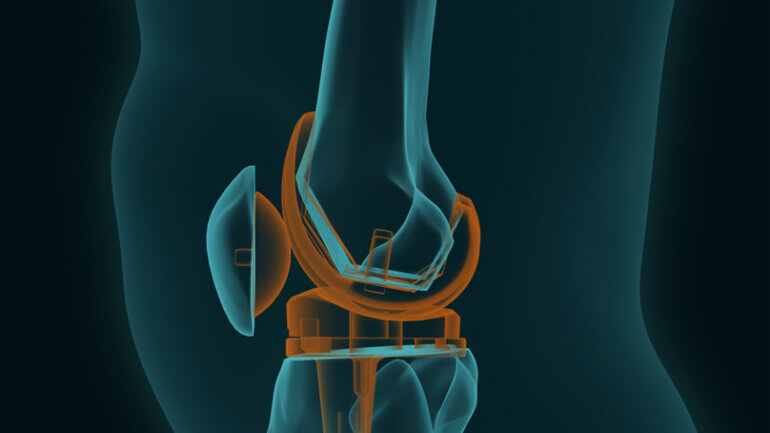

Η ολική αρθροπλαστική γόνατος αποτελεί τη μοναδική οριστική θεραπεία της οστεοαρθρίτιδας τελικού σταδίου.